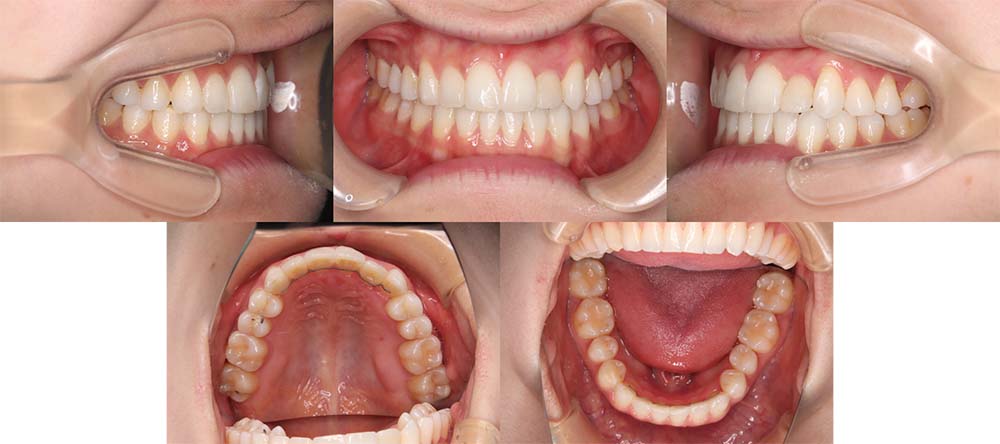

| 症例分類 | 下顎前突、開咬 |

| 診断名 | 上下叢生を伴う開咬 |

| 主訴 | 歯がガタガタ、前歯に隙間があってうまく噛めない |

| 年齢 | 18歳4ヶ月 |

| 性別 | 女性 |

| 抜歯部位 | 右上・左下の第一小臼歯と左上・右下の第二小臼歯 |

| 使用装置 | 表側のワイヤー装置 |

| 治療期間 | 2年9ヶ月 |

| 保定装置 | 固定式保定装置、取り外し式保定装置(8時間) |

| 費用 |

[検査・診断料] ¥49,500 [基本施術料] ¥792,000 [調整料] ¥4,400/回 [抜歯] ¥5,500/本 [保定装置] ¥55,000(税込) 抜歯や虫歯治療は他院にて費用が別途かかります。(抜歯¥4,000〜10,000/本)

他院にて「顎変形症のため手術併用での矯正治療が必要である」との説明を受け、当院を紹介されてご来院されました。骨格的にやや受け口傾向ではありましたが、手術を併用せず改善できる旨をご説明し、矯正単独で治療することにしました

上顎右側第一小臼歯、上顎左側第二小臼歯、下顎右側第二小臼歯、下顎左側第一小臼歯を抜去して治療を行いました。

左下は奥歯を前方に移動させる必要があったため、矯正用アンカースクリューと顎間ゴムを使用して噛み合わせを改善しました。左下の前方移動に時間がかかってしまい、治療期間が予定より伸びてしまいましたが、問題なく咬合させることができました。

下顎の親知らずは将来的に抜去した方が良いことを説明しております。